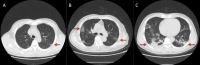

Results: A total of 1012 non-critically ill individuals with positive SARS-CoV-2 RT-PCR tests were included in the study. Thirty (of 1012, 3.0%) individuals were asymptomatic on admission. During hospitalization, 16 of 30 (53.3%) asymptomatic individuals developed different symptoms. Fourteen of 1012 patients (1.4%) remained asymptomatic from exposure to the end of follow up, with a median duration of 24 days (interquartile range 22-27). Fever (761 of 1012, 75.2%) and cough (531 of 1012, 52.4%) were the most common symptoms. Small patchy opacities (355 of 917, 38.7%) and ground-glass opacities (508 of 917, 55.4%) were common imaging manifestations in chest CT scans. One hundred patients (9.9%) were transferred to designated hospitals due to aggravation of illness. Diarrhoea emerged in 152 of 1012 patients (15.0%). Male, older age, diabetes, cardiovascular diseases, chills, dyspnoea, So2 value of ≤93%, white blood cell counts of >10 × 109/L and large consolidated opacities on CT images were all risk factors for aggravation of illness.